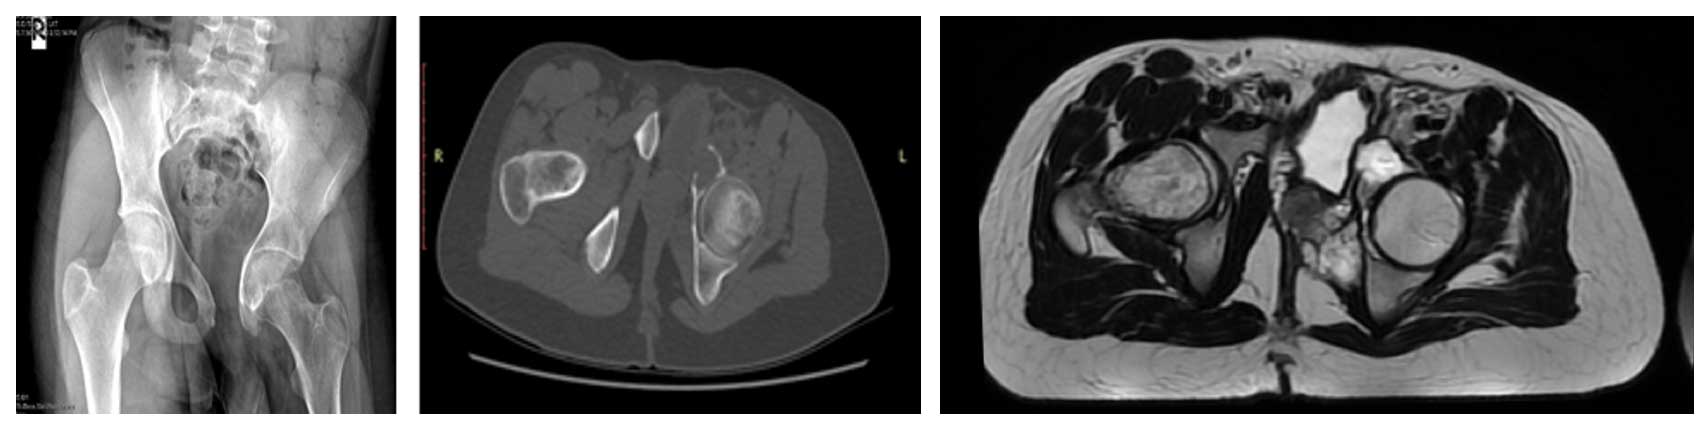

Ameliyat Öncesi: Röntgende uygulanmış rezeksiyon, tomografide asetabulum ön kısımda düzensizlik ve yeniklik, MR’da yumuşak doku kitlesi görülmekte.